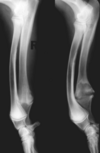

What is shown in these radiographs?

retained cartilaginous core

angular deformity of radius and ulna due to retained cartilaginous core